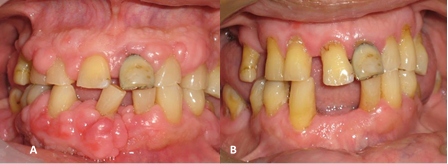

Caso clínico 3

Paciente de sexo masculino de 67 años quien acudió a consulta odontológica con periodoncista debido a incomodidad por presencia de abultamiento en encías inferiores (Figura 3). Refirió tener antecedentes de hipertensión arterial hace más de 20 años, tratada con nifedipino 10mg/8 horas. Al realizar examen clínico se observó aumento del volumen de la encía marginal, papilar y encía adherida tanto en maxilar inferior, específicamente a nivel de OD# 33, 41, 44, 45, de aspecto lobulado bastante marcado, y de color rojo intenso. Además, se encontró ausencia de OD# 42; movilidad dentaria en OD# 41. La encía marginal tenía aspecto lobulado, color rosa pálido en maxilar superior, a nivel de OD# 12, 13, 21, 22 (Figura 3A). El procedimiento quirúrgico se realizó sin complicaciones. Luego de 15 días de evolución, se evidenció ausencia de volumen de encía y tejidos sanos (Figura 3B).